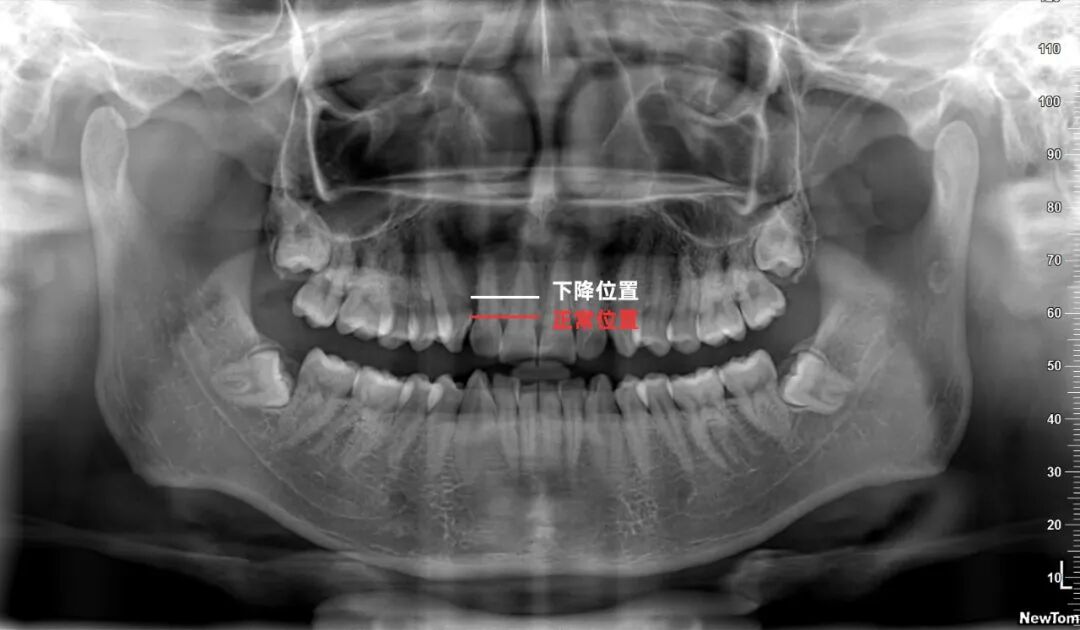

一般正常情况下,牙齿周围是被牙龈包裹没有很大间隙的,即牙槽骨线为红色线标注位置。而图中牙槽骨那根线已经明显下降,且牙齿和牙齿之间有黑色阴影,说明有牙根暴露,牙槽骨吸收的情况,这种情况如不及时治疗就会引发牙齿脱落。